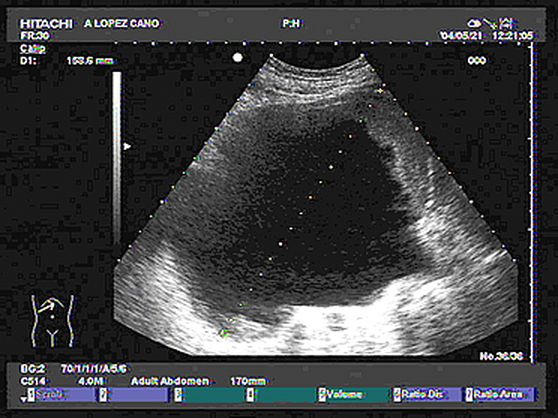

7.5. Patología anexial

Dr. A. López Cano, Dr. M. Tejada Cabrera (Cádiz)